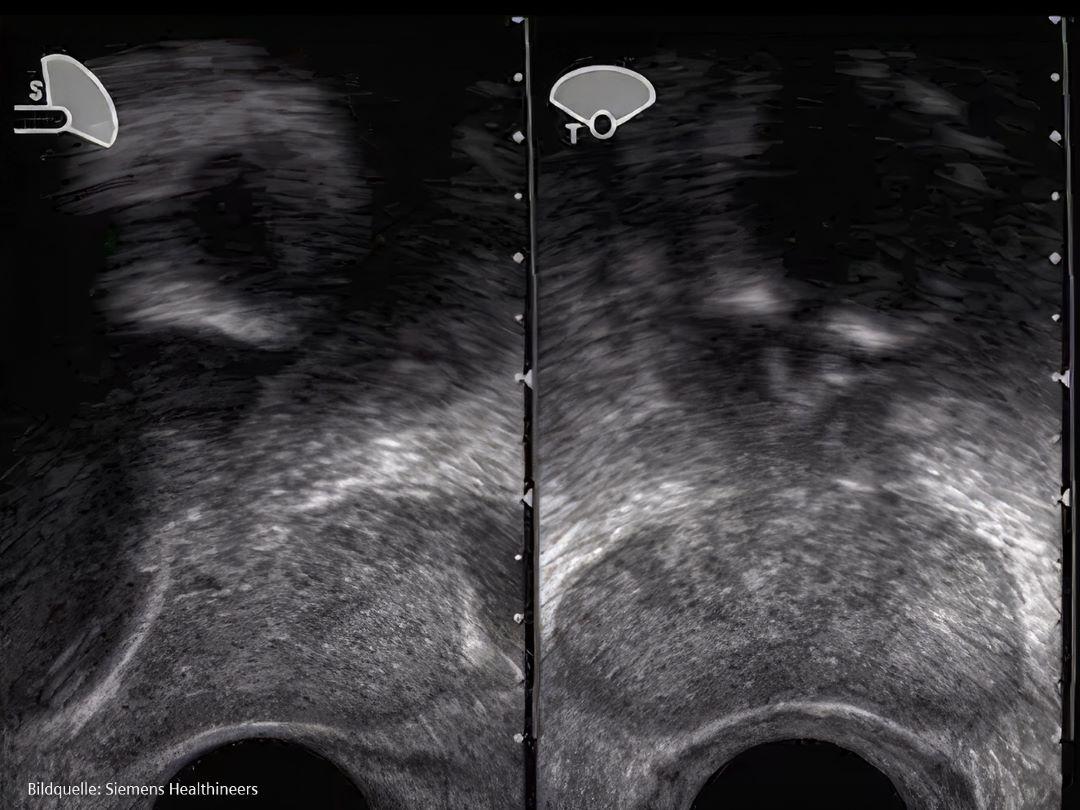

Diagnose und Staging

Was passiert, wenn Ärzt*innen vermuten, dass ein Patient Prostatakrebs haben könnte?

Für eine Diagnose wird der Patient nach den oben beschriebenen Symptomen und nach möglichen Risikofaktoren einschließlich seiner Familiengeschichte befragt. Im Falle eines Verdachts können Ärzt*innen einige Tests anordnen.